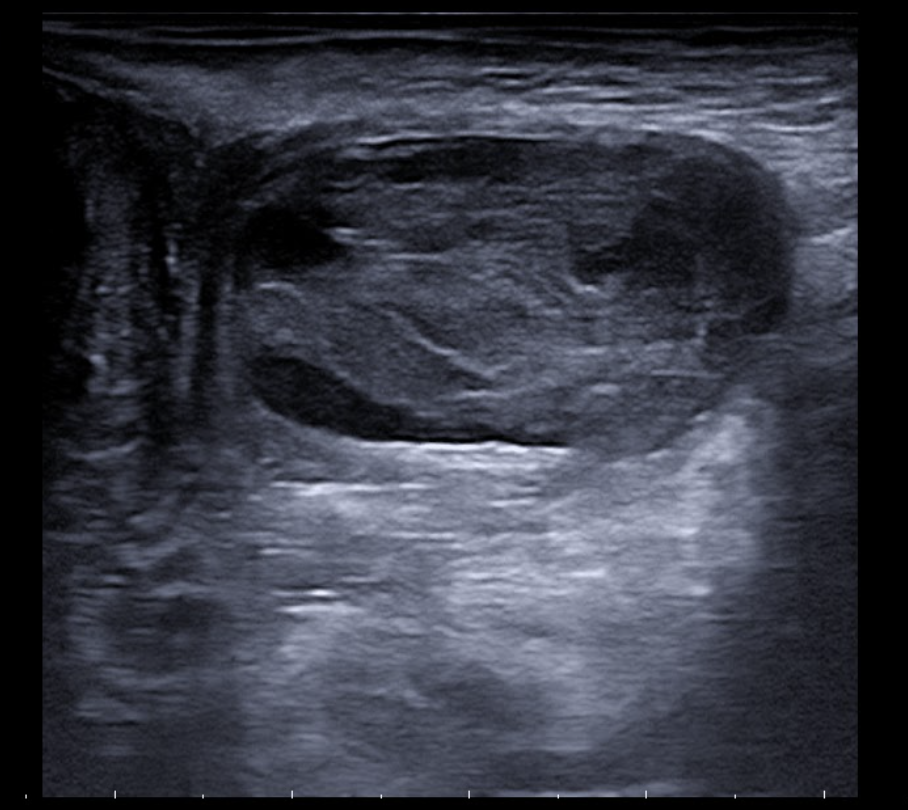

Se realiza ecografía con sonda lineal, apreciándose imagen ovalada con bordes bien definidos de contenido heterogéneo y sin captación Doppler, compatible con absceso localizado en tejido subcutáneo del labio mayor izquierdo. No se observa afectación de planos profundos, ni comunicación hacia región perianal o canal anal. No se identifican fístulas.